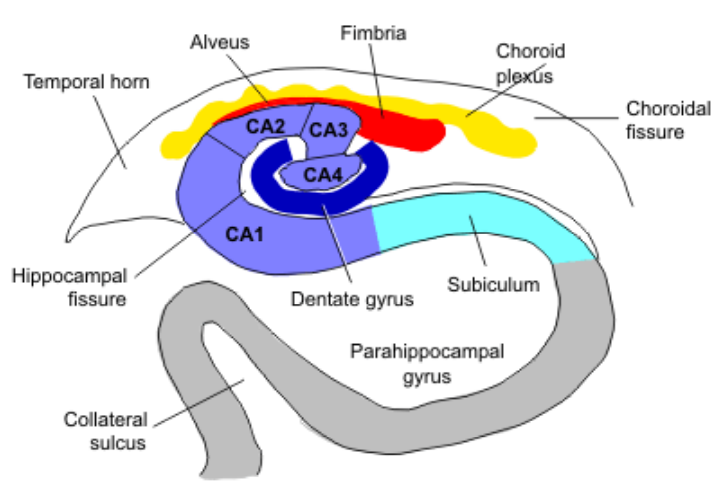

How are the different parts of the hippocampus important in different diseases?

Different areas of hippocampus can break down differentially in different diseases

Briefyl describe the neuropathology of temporal lobe epilsepsy?

Hippocampal sclerosis: cell loss, gliosis (scarring), hardening